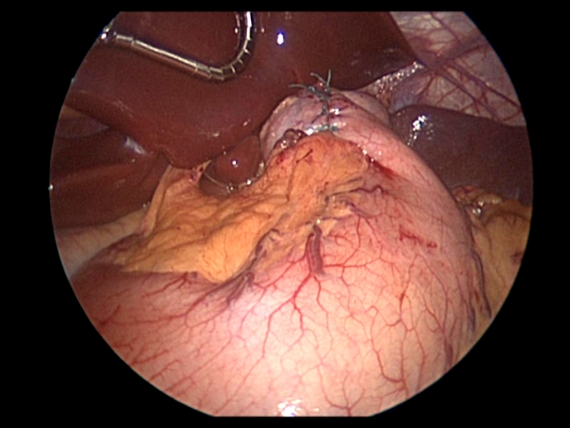

The omentum is a fatty apron that serves a protective role and helps filter immune responses to gut bacteria.